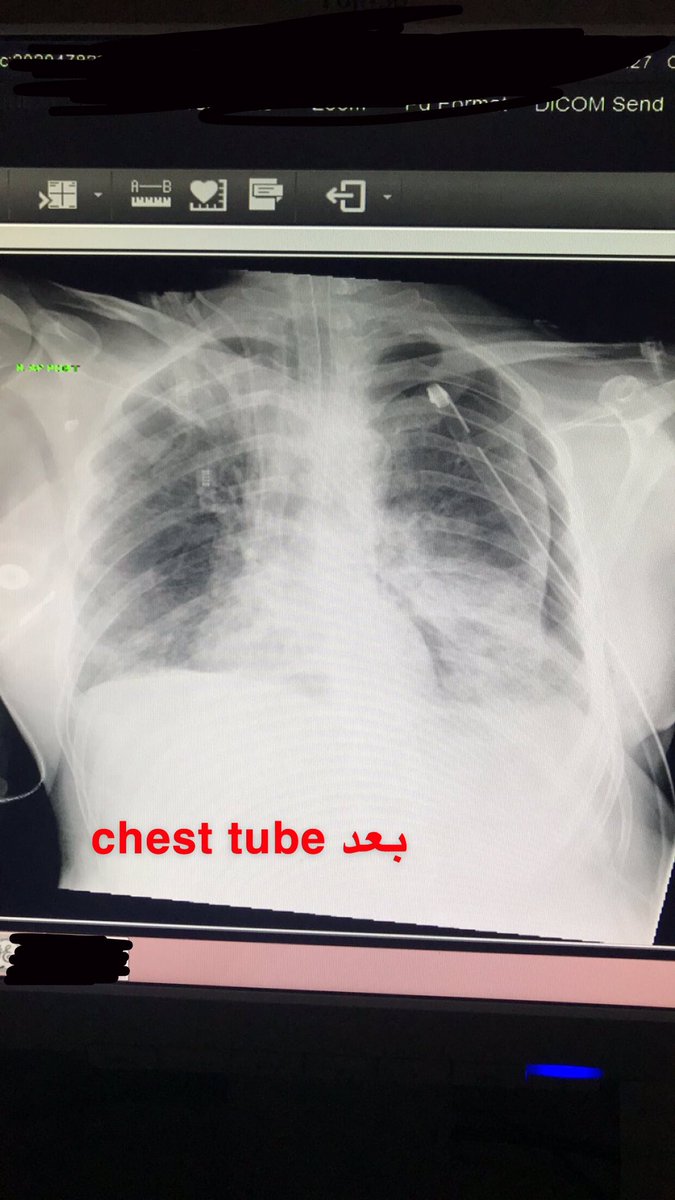

وأكلم الراديولجست اعطيه رقم المريض واقوله اكتب التقرير سريع وخلصه في خمس دقايق بعدها جوالفريق الطبي كامل و ع طول أنبوب chest tube لأن pneumothorax تسبب نقص للأكسجين و انخفاض ضغط الدم وممكن تؤدي الى الوفاه لو ما لحقو عليه وبالعاده ماراح يعرفون لأن التقرير يحتاج ثلاث ساعات⬇️

والحمدلله بعدها رجع الصدر للوضع الطبيعي وتم انقاذ المريض وطبيب المريض قالّي بفضل الله ثم إنت هالمريض عايش حسّيت بشعور جميل إنك تكون السبب الأول في انقاذ حياة مريض مع ان ماهي مسؤوليتي وقتها ولكن عرفت أهمية انك تشوف الصورة قبل تطلع لان ثانيةوحده ممكن تنقذ فيها مريض على وشك الموت⬇️

خصوصاً انها جت في يوم مبارك زي هاليوم وتذكرت الآية الي تقول .. وَمَنْ أَحْيَاهَا فَكَأَنَّمَا أَحْيَا النَّاسَ جَمِيعاً .. وهذي صورتين لما قبل الحالة وبعد والحمدلله حمداً كثيرا 🖤